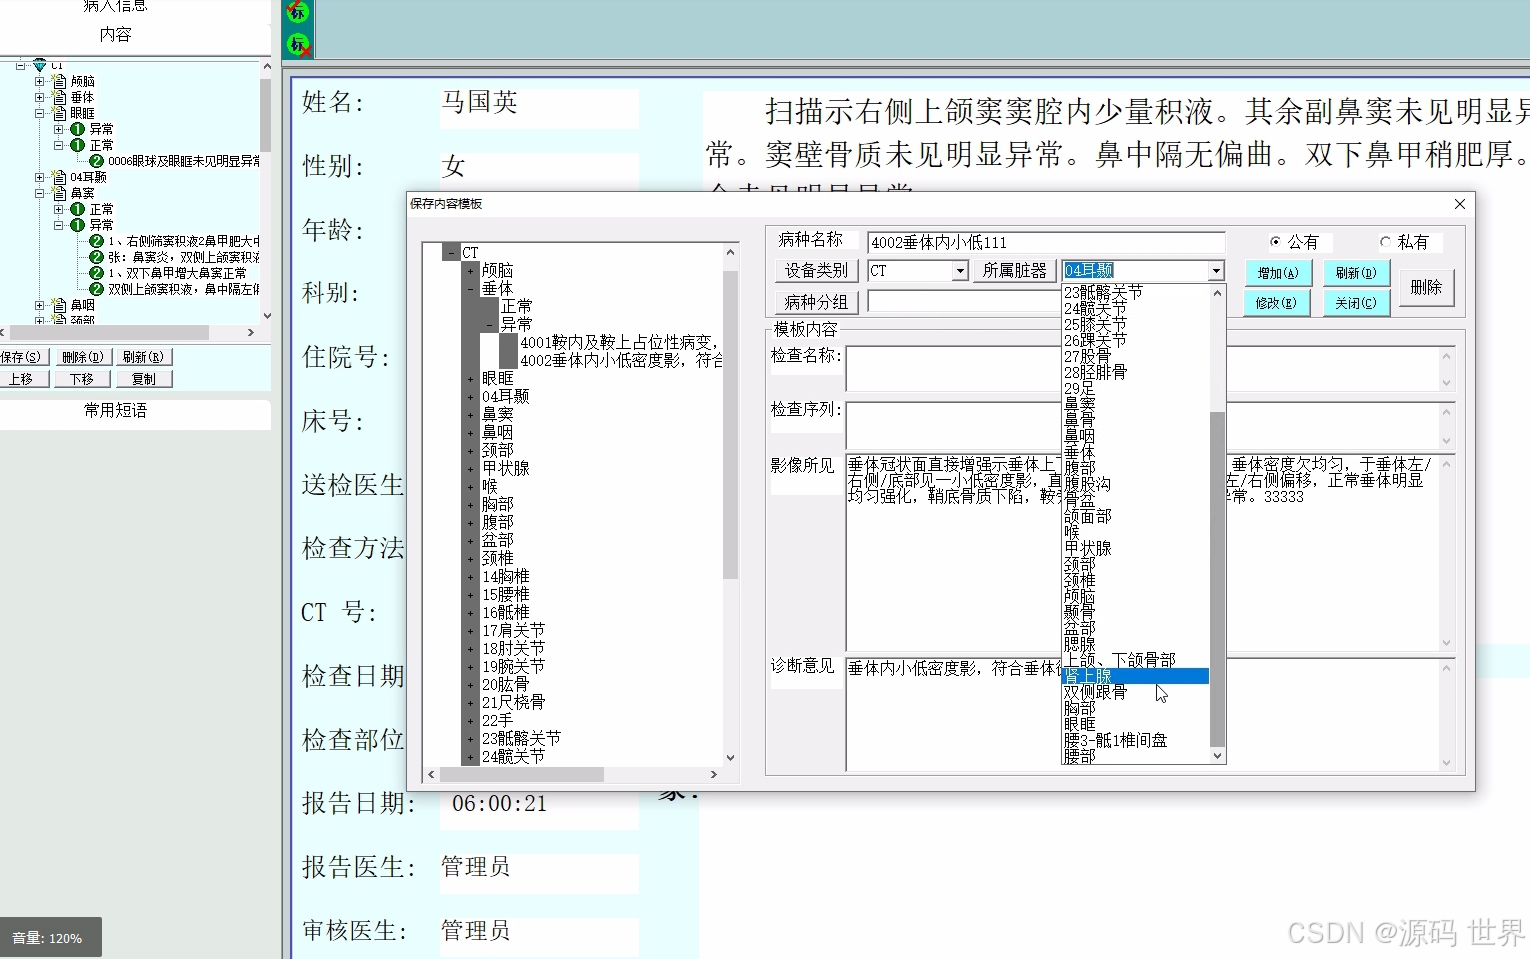

医学影像工作站主要用于从PACS服务器快速调阅影像,对调阅的影像进行后处理,影像标注,测量,胶片打印等功能。医学影像工作站和诊断报告工作站可以共同组成双屏工作站,用于影像科室书写诊断报告,替代原有的胶片+灯箱+ 纸笔+ 手写的工作方式。

PACS可进行影像质量、诊断报告质量控制管理。当影像检查完成后,由技术负责人通过质量控制工作站对影像质量进行评审,并可进行质量分析。在报告审核过程中,可对报告修改痕迹进行保留,以提供初诊报告质量评审,并可通过网络共享调阅,提高整个科室的诊断水平。